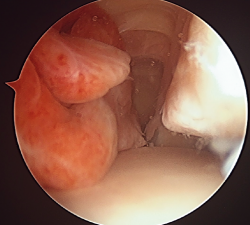

Sinovitis vellonodular pigmentada de tobillo

Pigmented villonodular synovitis of the ankle

- Sinovitis vellonodular pigmentada de tobillo